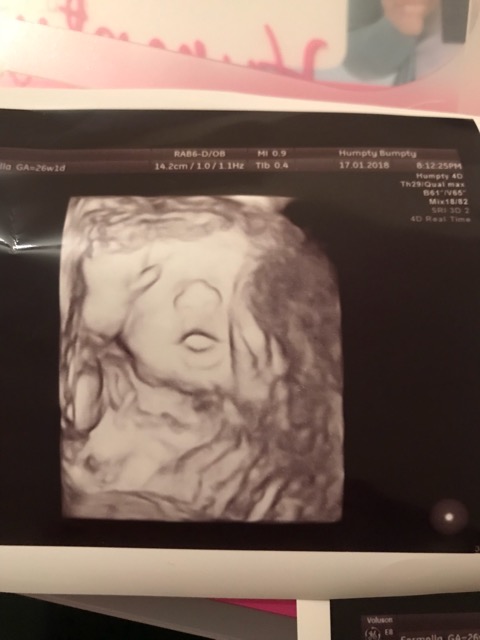

Daddy’s double👶🏽💙

26 + 2. Our gorgeous little boy. Defo the double of his dad, look at that nose 😫😻💙